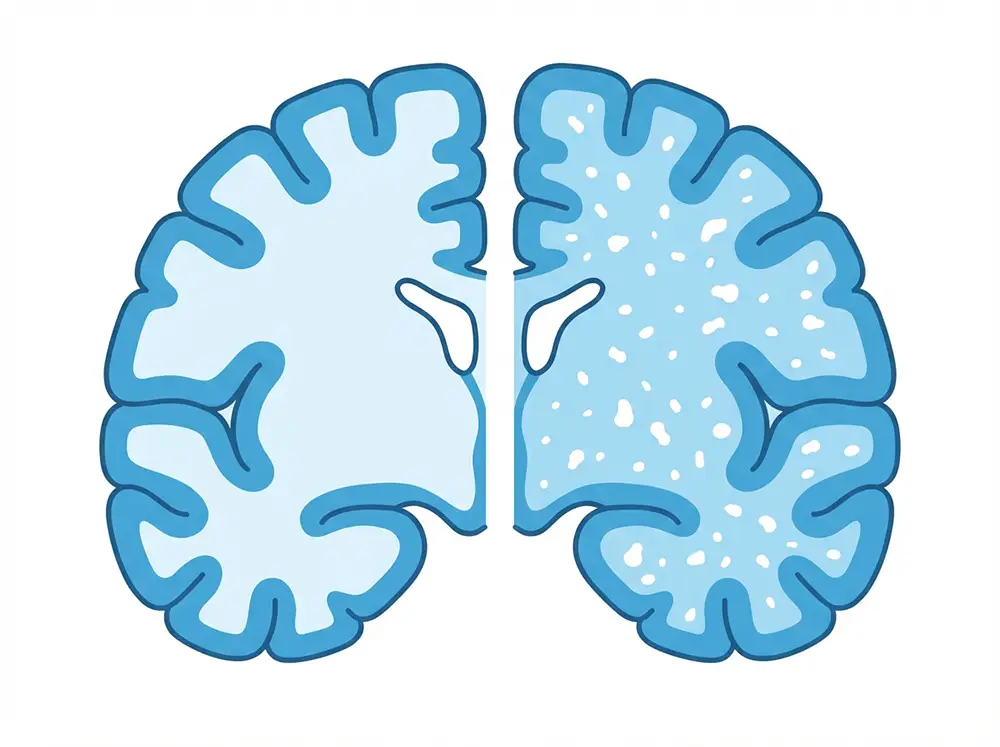

La leucopathie vasculaire désigne des anomalies de la substance blanche du cerveau, détectées principalement lors d’un examen d’IRM cérébrale. Le terme vient du grec : leuco signifie blanc et pathos signifie maladie. Mais attention à l’interprétation : il ne s’agit pas d’une maladie en soi, mais d’un signe d’imagerie révélant une atteinte des petites artères qui irriguent le cerveau. On parle aussi de leucoaraïose, de leucoencéphalopathie vasculaire, ou encore, dans la terminologie la plus récente, d’hypersignaux de la substance blanche (HBS).

Elle est composée de fibres nerveuses appelées axones, chacune enveloppée dans une gaine grasse isolante : la myéline. Ce revêtement accélère la transmission des signaux nerveux entre les différentes zones de la substance grise, là où se trouvent les corps cellulaires des neurones. La substance grise traite l’information ; la substance blanche la transmet. Une anomalie de la substance blanche perturbe donc directement les échanges entre les différentes régions du cerveau. Quand les petits vaisseaux qui l’irriguent sont endommagés, les fibres nerveuses souffrent et des lésions apparaissent progressivement.

Par ailleurs, des maladies inflammatoires comme la sclérose en plaques peuvent produire des lésions de la matière blanche d’aspect similaire à l’IRM, mais d’origine très différente. On parle alors de leucopathie inflammatoire ou démyélinisante. D’autres causes non vasculaires existent : toxiques, métaboliques, tumorales ou encore infectieuses. C’est pourquoi l’interprétation du contexte clinique est toujours indispensable, au-delà du seul résultat d’imagerie.